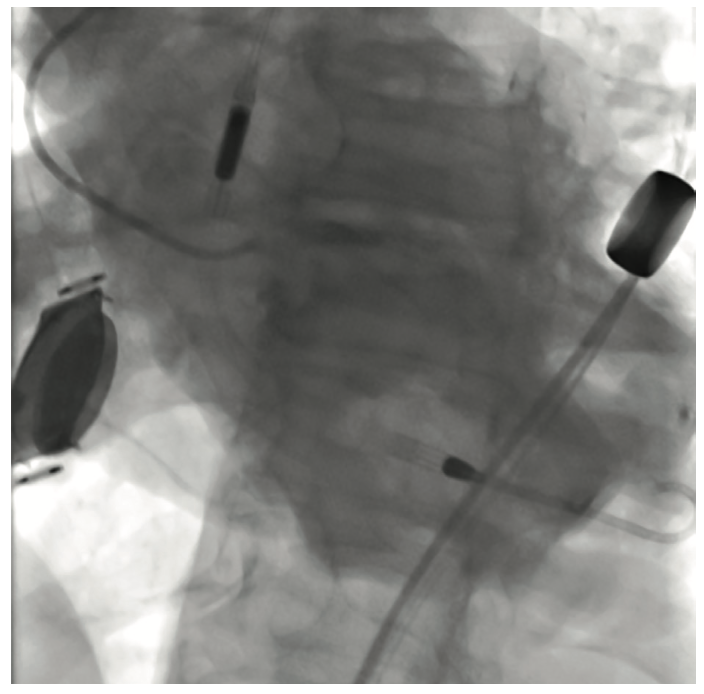

The initial interventional attempt via a transradial approach was unsuccessful due to significant vessel tortuosity. Therefore, a high risk protected PCI was attempted via left femoral access using an Impella 2.5L device (Abiomed) for left ventricular support. The Impella 2.5L was placed via the right femoral access. Before the engagement of coronary arteries, the patient had deteriorated clinically with hypotension and Impella support dropping to 1.4L. Subsequently, the patient went into VT/VF arrest, requiring cardiopulmonary resuscitation (CPR). The patient was emergently intubated. During active CPR and VT storm, selective injections of the left main coronary artery were performed, revealing total thrombotic occlusion of distal left main artery. The patient underwent multiple percutaneous transluminal coronary angioplasties of the left main, ostial and mid LAD, and LCx (OM1) lesions. This was then followed up with stenting of the mid left main into the ostial LAD and LCx (OM1) branch. The coronary interventions were performed during CPR. The patient received a total of 13 defibrillator shocks, and was given intravenous amiodarone and lidocaine pushes during CPR. Return of spontaneous circulation was obtained after 45 minutes. Due to extensive PAD, the Impella device was removed and an intra-aortic balloon pump was placed via a left femoral approach for continued hemodynamic support.